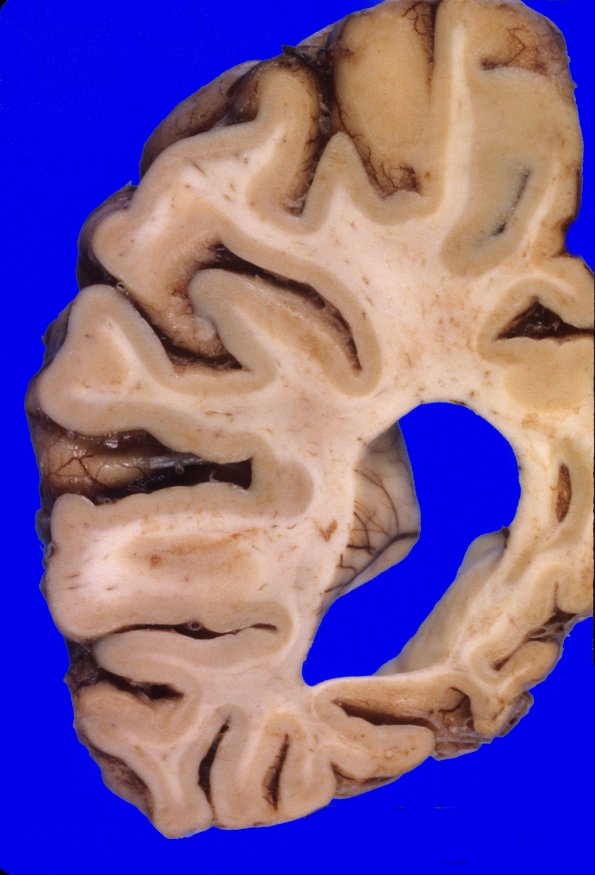

Coronal sections confirm the degree of diffuse cortical atrophy with narrow gyri and wide sulci with a large amount of ventricular dilatation and blunting. The cerebral white matter is diffusely firm to palpation. The corpus callosum is extremely thin.